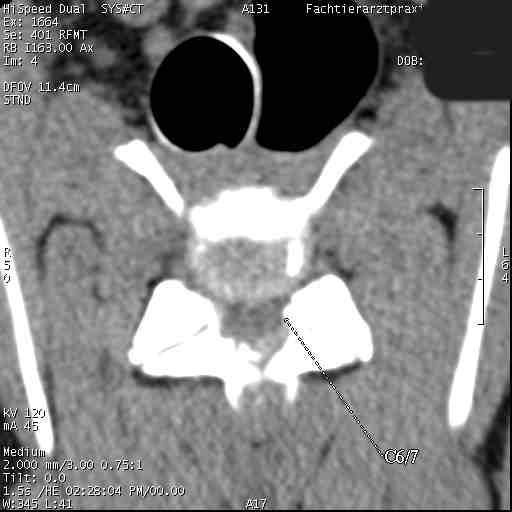

Im folgenden Beispiel sieht man computertomografische Bilder der Halswirbelsäule einer Dogge mit folgender Diagnose: Knöcherne Stensoe C3/4 [= 3./4. Halswirbel], sanduhrförmige Kompression des Myelons auf der Höhe C3/4, Bandscheibenvofall C6/7 [= 6./7. Halswirbel], Myelon mit seitlicher Abweichung nach links : Im Ergebnis eine Halswirbelstenose an den beiden Stellen mit Kompression des Myelons, die zu den Lähmungserscheinungen führt.